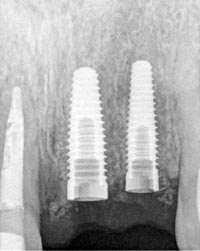

Using computer-guided surgery, our Toronto dentist determines the four best locations for implants and inserts them into the bone. An implant is a small titanium screw that fits inside your jawbone and acts like a root of a tooth.